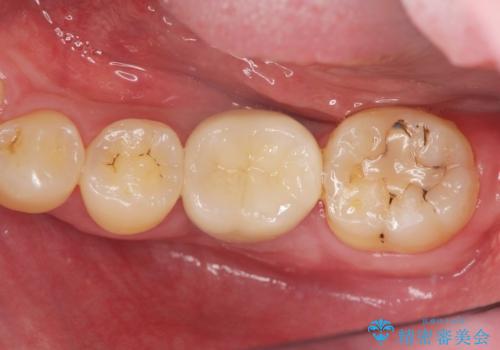

- 「長年虫歯放置した結果、抜歯となってしまった左下奥歯に歯を入れたい」、と希望され来院されました。

前後の歯は虫歯も治療歴もないため、前後の歯を削らなくてはいけないブリッジではなくインプラント治療による咬合機能回復を計画します。

- 46.2万円(仮歯・ストローマンインプラント・チタンカスタムアバットメント・ジルコニアクラウン)費用は治療当時の料金となります